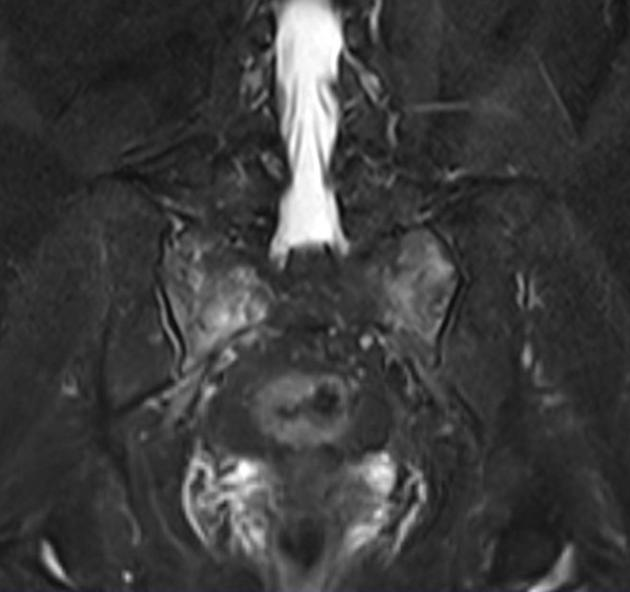

磁共振检查:

STIR

影像表现

2、单侧或双侧骶骨翼骨皮质断裂,见迂曲纵行骨折线,大致与骶髂关节平行(双侧多见);

3、骶骨体部看见骨折线

4、冠状位上述骨折形成 “H”型 ,故有人称东风本田征(为了方便记忆)

5、骨折线一般较为模糊,看见看到骨质硬化;

6、磁共振上可以发现骨折线周边明显的骨髓水肿,增强扫描明显强化

磁共振影像表现